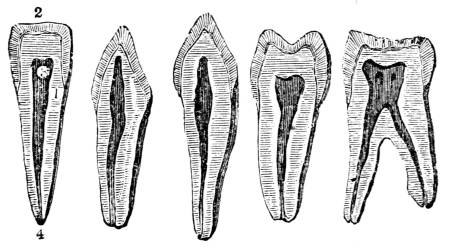

1. The trachea. 2. The right and left bronchus; the left

bronchus showing its division into smaller and smaller

branches in the lung, and the ultimate termination of the

branches in the air vesicles. 3. Right auricle of the heart.

4. Left auricle. 5. Right ventricle. 6. The aorta arising from

the left ventricle, the left ventricle being in this diagram

concealed by the right. 7. Pulmonary artery arising from

the right ventricle and dividing into, 8. The right, and

9. The left branch. The latter is seen dividing into smaller

and smaller branches, and ultimately terminating on the

air vesicles. 10. Branches of one of the pulmonary veins

proceeding from the terminations of the pulmonary artery

on the air vesicles, where together they form the net-work

of vessels termed the Rete Mirabile. 11. Trunk of the

vein on its way to the left auricle of the heart. 12.

Superior vena cava. 13. Inferior vena cava. 14. Air vesicles

magnified. 15. Blood-vessels distributed upon them.

to that of respiration in the animal, in which

carbonic acid is always generated and expired, is